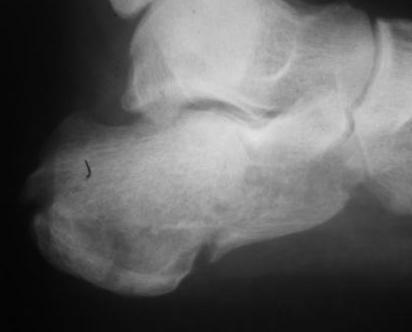

И чем вам не нравится ORIF?... Не нашел первоначальный снимок, но очень похож на представленный. Есть только после операции. Через 6 нед. встал и пошел без боли!

IMG_0221.JPG